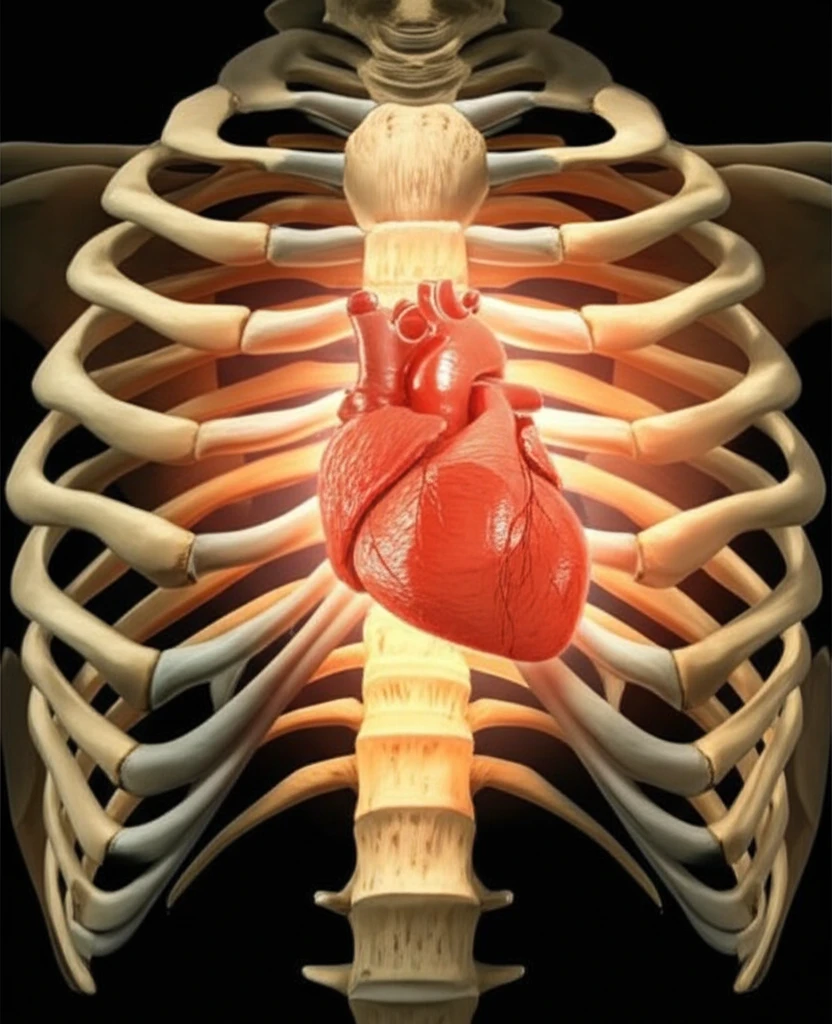

For individuals facing end-stage heart failure, a heart transplant represents more than just a medical procedure; it's a lifeline. While advancements in left ventricular assist devices have provided crucial support, heart transplantation remains the gold standard for extending and improving the quality of life. Unfortunately, the demand for donor hearts far exceeds the supply. It's estimated that over 20,000 people in the United States could benefit from a heart transplant, yet only a fraction receive one each year.

This disparity highlights a critical need to expand the donor pool safely and effectively. One potential solution lies in re-evaluating the use of hearts from early adolescent donors (individuals aged 10 to 14). These hearts, often not considered for pediatric recipients, could offer a valuable resource for adult patients in need. However, concerns about hormonal factors and heart development have historically limited their use.

Traditionally, the hearts of early adolescent donors haven't been widely used for adult transplants due to concerns about their development and hormonal activity. Early adolescence is a period marked by significant hormonal changes that fuel growth spurts, sexual development, and the emergence of secondary sexual characteristics. Some experts have theorized that the hormonal surge during this time also impacts heart growth, increasing both the thickness of the heart walls and overall contractility.